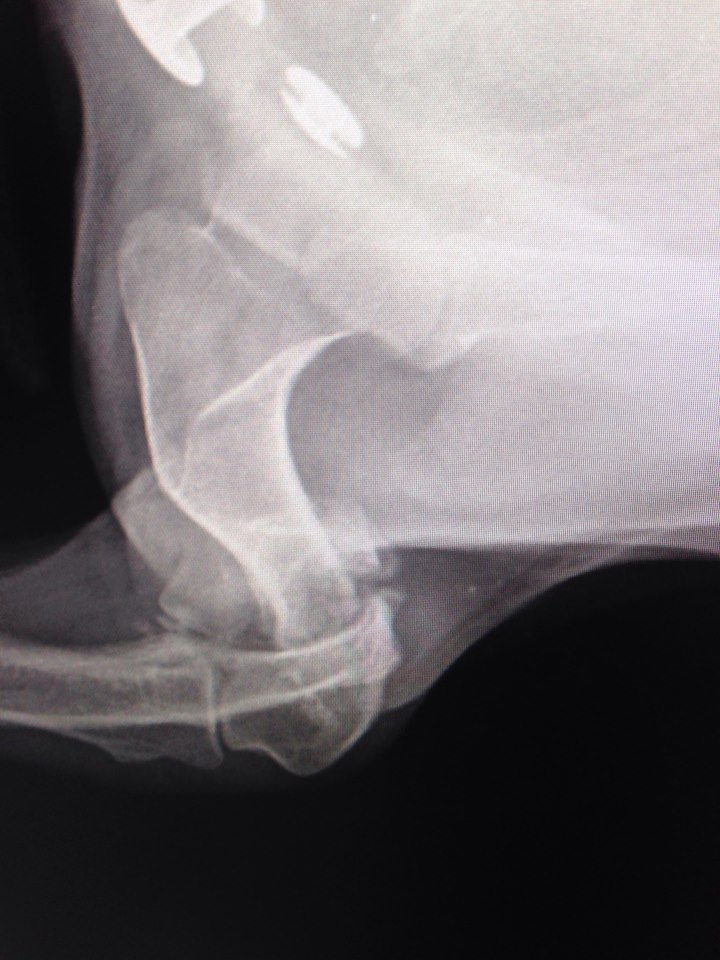

В клинику поступила с жалобами на отсутствие опоры левой грудной конечности. При осмотре обнаружилось, что у собаки нарушены анатомические контуры левого локтевого сустава и при манипуляциях с этим суставом животное испытывает боль.

Рентгенографические снимки в прямой и боковой проекциях показали, что Элли перенесла полтора-два месяца назад перелом латерального мыщелка левой плечевой кости.

Этот перелом не был должным образом пролечен. Собаке нужно было выполнить хирургическое лечение, так как такие переломы лечатся только оперативно. Все внутрисоставные переломы должны быть хирургически собраны максимально точно. Это обеспечивает полноценность работы сустава. Если нет адекватного анатомического сопоставления, будет развиваться остеоартрит, сустав придет в негодность. В данном случае собаке просто наложили гипс. За прошедшее время поверхности срослись в том виде, в каком были при переломе. Сустав полностью был разрушен.

Для того, чтобы убрать боль собаке и позволить ей опираться на конечность, мы выполнили артродезирование левого локтевого сустава.

Смысл в том, что мы сращиваем сустав, т.е. создаем условия, которые вызывают срастание поверхностей сустава. Благодаря этому будет обеспечена опорная функция конечности и уйдет боль. Ожидаем получить хороший клинический результат, потому что собака маленькая.

В ходе операции выполнили доступ к суставу, убрали весь хрящ с помощью бормашины. Затем осуществили аутотрансплантацию губчатой кости: перенесли кость из внутренней части левого плеча (губчатая кость) в полость левого локтевого сустава. После чего выполнили фиксацию. Часть фиксации находится внутри - это спицы. Основная часть фиксации находится снаружи - внешний фиксатор. Рассчитываем, что примерно через два с половиной месяца плечо срастется с предплечьем, т.е. произойдет полное сращивание локтевого сустава. Тогда и демонтируемых внешний фиксатор. Внутренняя фиксация извлекаться не будет.